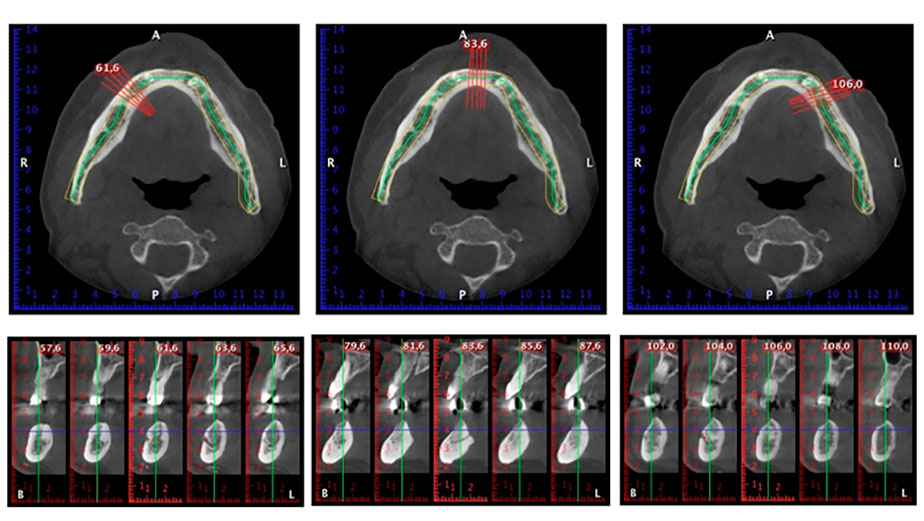

Направи се скенер с триизмерна компютърна томография (CBCT, Planmeca), за да се подпомогне планирането и да се намалят рисковете. Той показа, че качеството и количеството на наличната кост са достатъчни за операцията и имедиатното възстановяване, използвайки Fast & Fixed метод. Следвайки протокола за тази концепция, имплантите са поставени на 35, 32, 42 и 45 позиция. Ангулирането на дисталните импланти до 45° промени профила в задната зона и осигури по-голяма поддръжка в многоъгълната зона (Фиг. 3).

Fast & Fixed метод

Фиг. 3